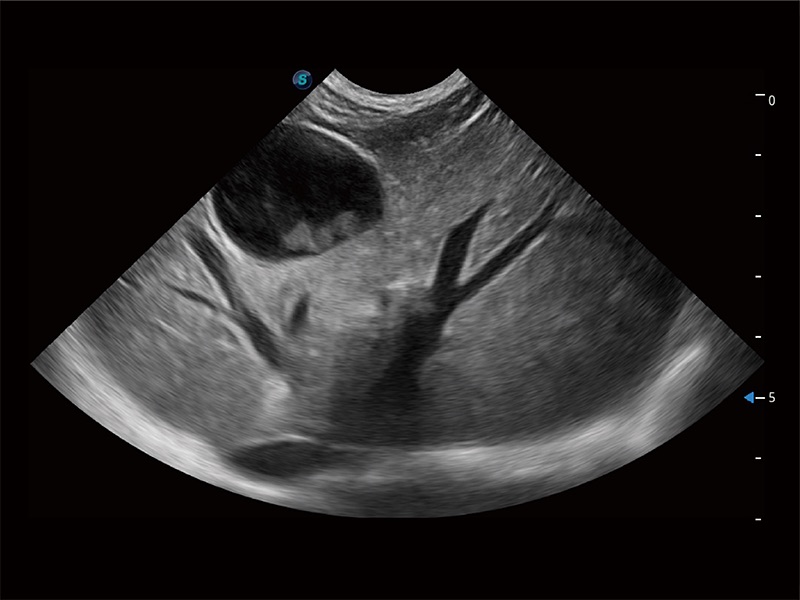

动物是人类最亲密的朋友和最值得信赖的伙伴。竞技宝(JJB)官方网站也一直致力于探索动物专用的超声影像解决方案。全新推出的ProPet系列,是竞技宝(JJB)官方网站在动物超声影像智能化、专业化、精准化的一次跨越式革新。动物不能用言语来表述自己的不适,通过超声影像,ProPet系列搭建了动物医生与不同物种沟通的“桥梁”,为动物医生注入了“治愈之力”。 ProPet 80 是竞技宝(JJB)官方网站匠心打造的一款高端动物专用彩超,采用性能卓越的全新硬件架构,极大提升超声系统的运行效率和数据处理能力,帮助动物医生从容应对日益增多的挑战性病例和日益多样化的临床需求。

高性能和先进的临床应用工具可以为动物医生提供临床信心。ProPet 80 搭载了先进的腹部和浅表应用工具,帮助医生在日常临床实践中发挥前所未有的作用。

ProPet 80 全新的动物超声智能软件和丰富的探头群,为动物医生提供了高清晰度和精细分辨率的图像,无论在宠物、马科、畜牧还是实验室动物等应用中都可以轻松应对,为您的日常工作带来满意的体验。